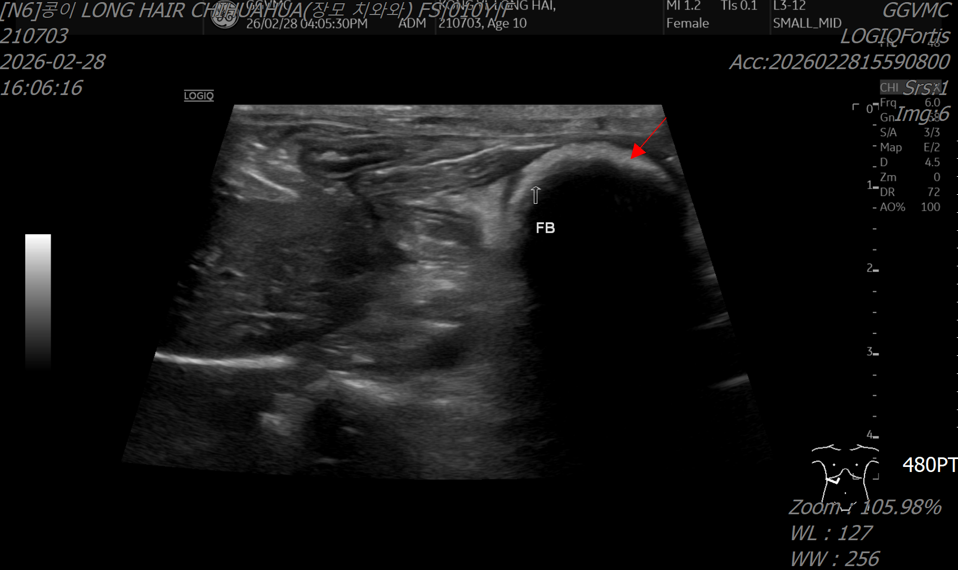

- 초음파 검사에서도 소장 폐색이 의심되는 소견이 확인되었습니다.

초음파 검사: 소장 폐색 의심 소견

<초음파 검사>